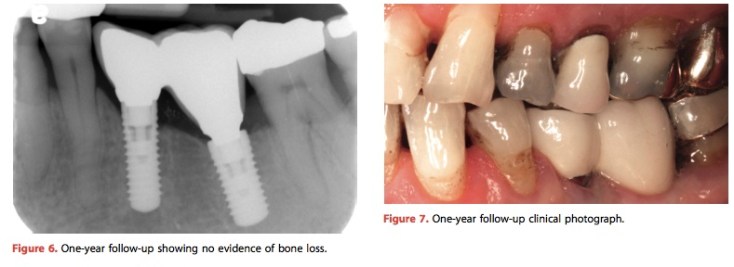

這個case report很有意思, 值得讓有在做植牙補綴的醫師參考. 在bone level的植體設計中, 多少會有platform switching的部分. 但是如果不幸bone level implant種的不夠深, 那反而容易卡東西, 要怎麼做?

這篇UBC的case做了platform unswitching, 就是在該要有內凹的部分用貴金屬casting出一個環, 將這個凹陷處整個包住. 雖說不好看但是在清潔上就避免髒東西卡在那凹陷處. 這樣的想法確實是實用而且不會很貴, 但是要配合screw retained prosthesis.